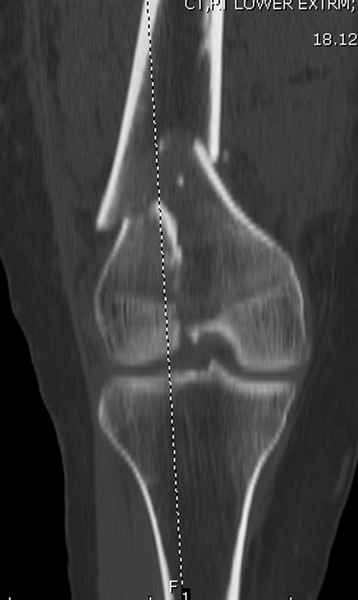

Привет из Нижнего Новгорода! К нам поступил пациент 25 лет с закрытыми переломами обеих бедренных костей, прошел месяц после травмы. Слева - внутрисуставной перелом, поэтому выбор здесь очевиден, открытая репозиция, стабильная фиксация, скорее всего LCP DF, а справа - мнения учёных, как говорится, разошлись. Лично я, как лечащий врач, за закрытый интрамедуллярный остеосинтез DFN. Со мной согласна половина коллектива, другая - за интрамедуллярный остеосинтез (DFN,UFN) но с открытой реопозицией, поскольку при закрытой методике все осколки останутся где-то сбоку, получится дефект и вдруг не срастется!Философский вопрос: что лучше - красивая рентгенограмма или сохранение кровоснабжения? Очень важно мнение коллег! Смирнов Алексей

Приветствую всех коллег!!Во первых слева хотелось бы видеть четкую боковую проекцию а лучше КТ. По р-мам есть сомнения насчет повреждения суставной поверхности. При подобных переломах даже внутрисуставных без смещения хорошие результаты показал закрытый ретроградный остеосинтез универсальным бедренным стержнем Деост.Кстати при внутрисуставном переломе возможно применение вместо винтов стягивающих болтов!!(См. метод.Деост).При переломе справа также стержень Деост. Однако без открытия Вам не удастся устранить интерпозицию, только промучаетесь!Из минимального разреза удалите интерпозициб и фиксируйте стержнем. Причем универсальный стежень Деост позволяет фиксировать дистально минимум на трех уровнях!